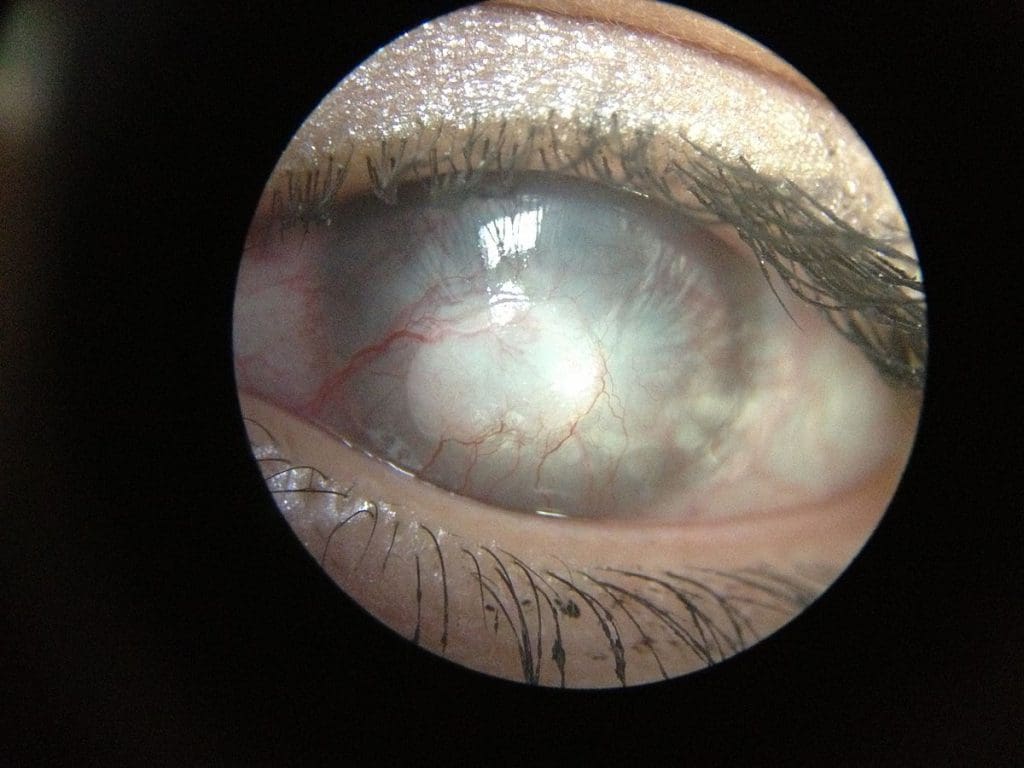

Corneal Scarring

What causes corneal scars?

Corneal scars may be the product of prior trauma, like injuries or infections, or they may arise as the result of certain disease processes, for example rare corneal dystrophies.

How do corneal scars affect my vision?

Corneal scars cause two basic problems – they undermine the clarity of the cornea, and they distort its shape. Normally, the cornea is an almost perfectly spherical, optically pristine instrument for projecting light into the eye, where it can be focused on the retina, so that images can be formed and passed to the brain.

Corneal scars, however, block the passage of light through the cornea. Furthermore, the light which does make it through the scar into the eye is typically distorted. As a result, the images formed on the retina are weak or washed out, rather than crisp and clear.